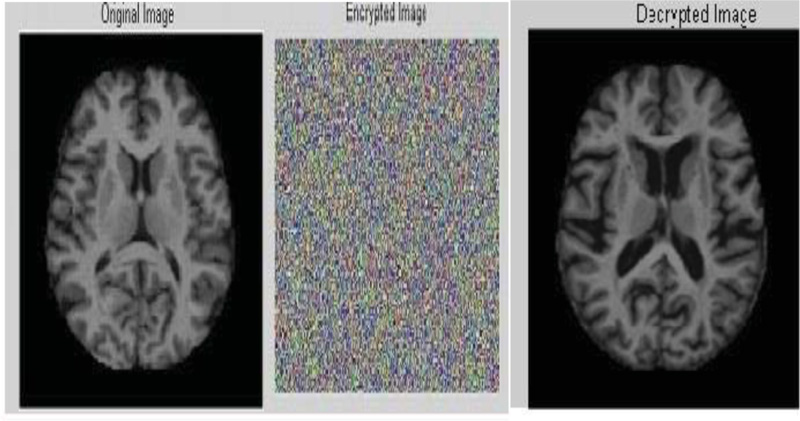

When the gateway is receiving the data, it can perform decryption to get back the original medical data. The successful authentication process is illustrated with sensor data and brain image as shown in Figs. (6 and 7).

If the authentication is successful, the receiver can generate the cypher key, which will match with cypher key generated by the sender side. Therefore, it is true to accept the decrypted data or image as original data. From the gateway, it is suggested to apply FBKM algorithm, and data will be transmitted to the destination under the successful case, as shown in Fig. (8).